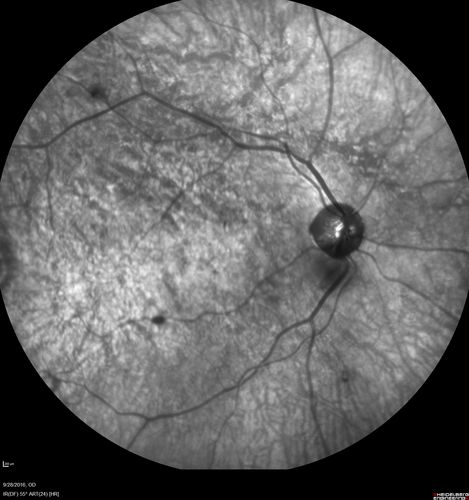

Macular Macroaneurysm with Coats Disease

61 year old man with increased leakage from macular macroaneurysm right eye